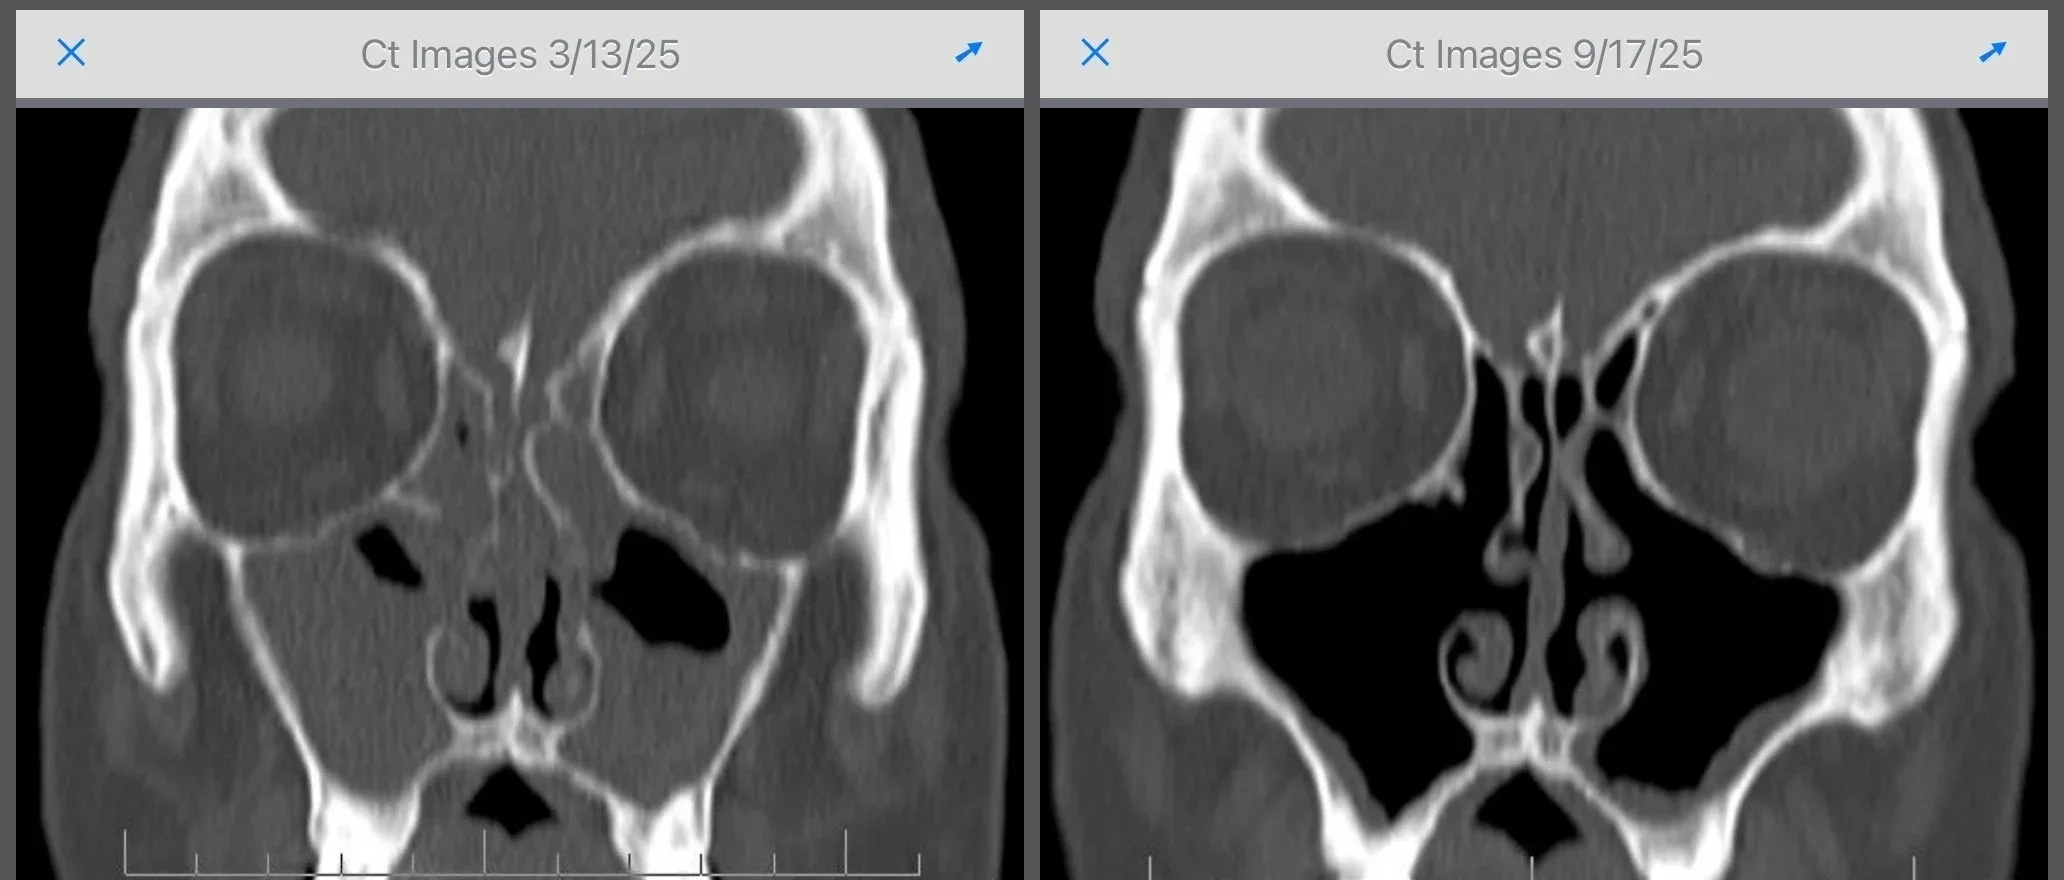

Above is a real example from our practice:

On the left is the BEFORE picture. This is after the patient has had sinus surgery, but then the polyps recurred.

On the right is the AFTER picture. This is after 6 months of biologic therapy. Grey stuff is polyps, black is air. Less grey and more black means less polyps. You don’t have to be a radiologist to know that this patient is feeling a LOT better.